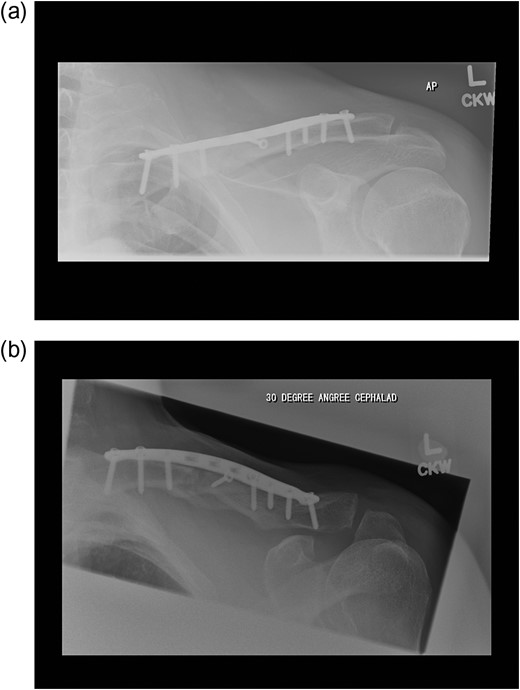

Plate fixation with a pre-contoured locking plate was performed under general anaesthesia. The clavicle was exposed through an infraclavicular transverse incision (~1.5 cm inferior to subcutaneous border). The platysma was incised and the supraclavicular nerve branches were identified superficial to the deep fascia. The pectoralis fascia was incised and reflected cranially to expose the superior aspect of the clavicle. It was noted that one of the supraclavicular nerves was passing through a foramen in the clavicle shaft. It was necessary to divide this nerve branch to permit appropriate plate positioning (Fig. 2).

Post-operatively he had some numbness around the surgical incision but experienced no pain. His fracture united by the 12th week (Fig. 3).